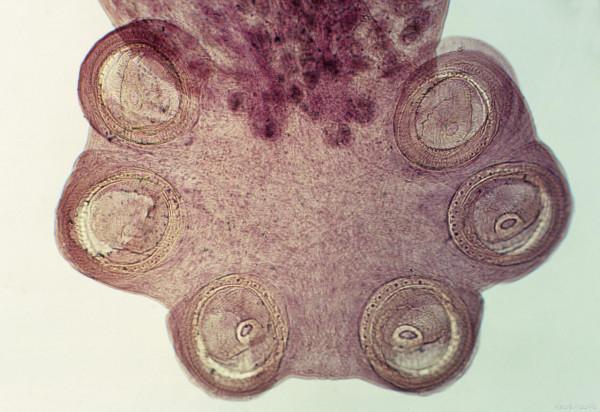

薑片吸蟲是由布氏薑片吸蟲寄生於豬和人的小腸內而引起的一種人獸共患的吸蟲病。

本病主要感染豬和人,蟲卵隨人或豬的糞便排出,在中間宿主體內發育成尾蚴,然後離開中間宿主,吸附到水生植物表面,脫去尾部形成具有感染力的囊蚴,經消化道感染人和豬,引起發病。